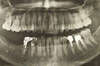

Cas d'extraction implantation immédiate et utilisation du laser Dio 500

Radio panoramique pré opératoire montrant la nécessité d'extraire la 45 qui présente une image apicale et une structure coronaire excluant son utilisation pour une nouvelle prothèse